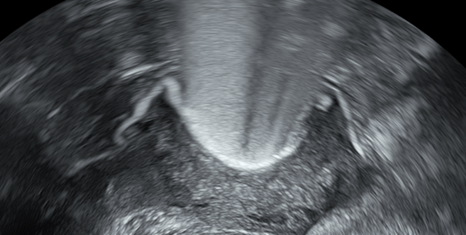

Trilaminares Endometrium

Dominater Follikel